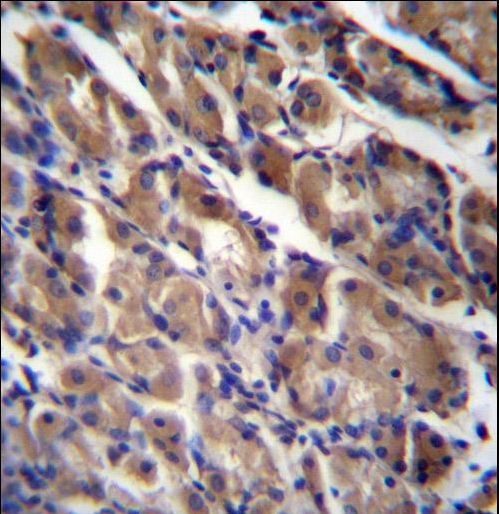

- Experimental details

- ABRA Antibody immunohistochemistry of formalin-fixed and paraffin-embedded human stomach tissue followed by peroxidase-conjugated secondary antibody and DAB staining.